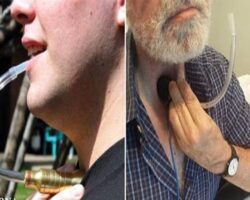

بیشتر بخوانید صدای رسا با حنجره مصنوعی

صدای رسا با حنجره مصنوعی تهران – ایرنا – محققان موسسه MARCS موفق به ساخت یک حنجره مصنوعی شده اندکه بدون نیاز به عمل جراحی، قادر به تولید صدای رسا ...